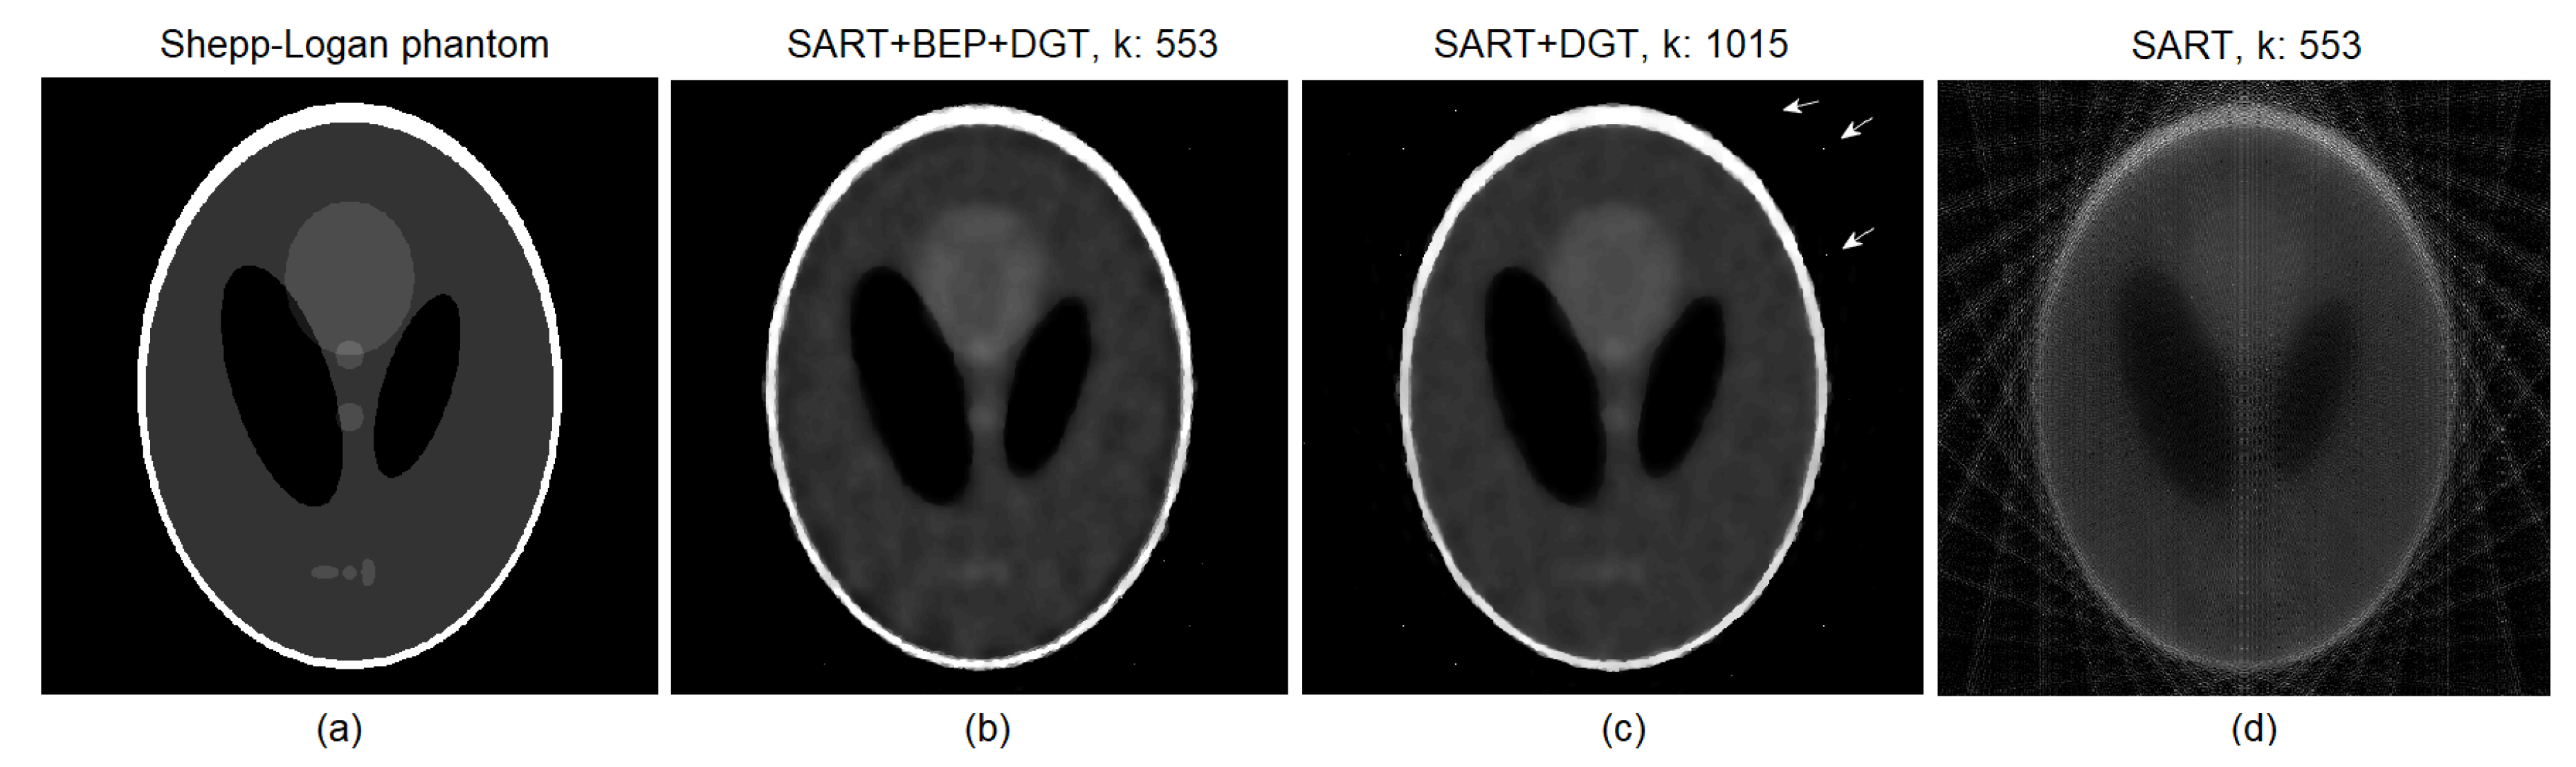

4. Experiments and Results

Low Dosage Tests and Results